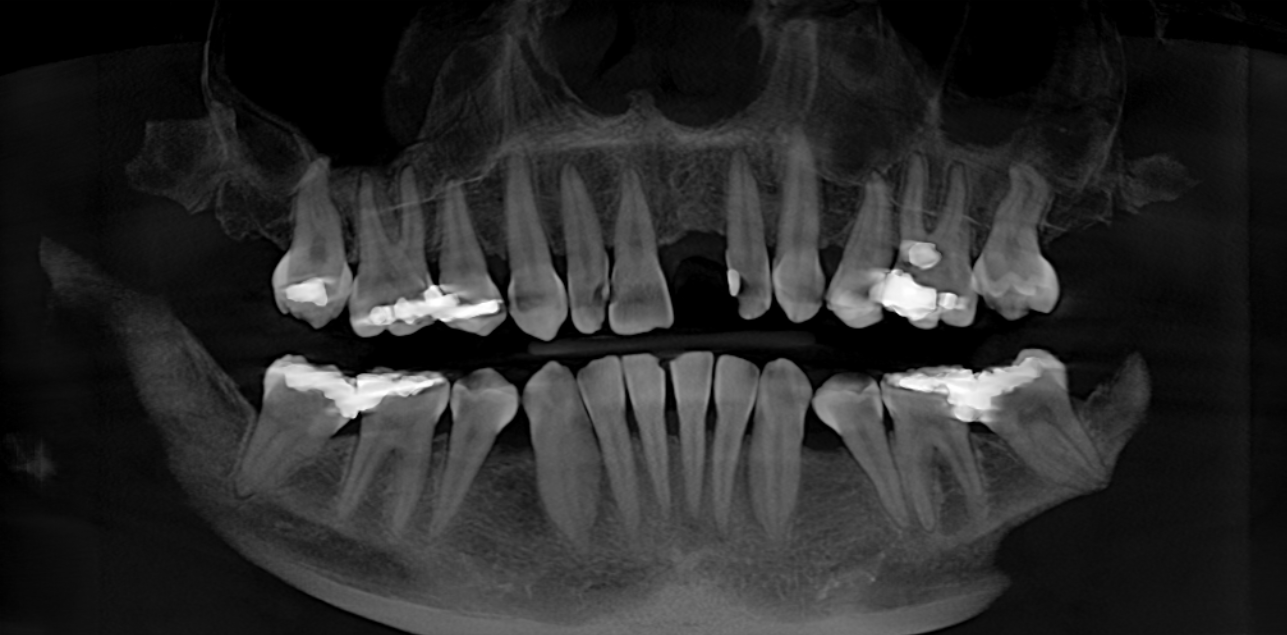

We start with a comprehensive full mouth examination, digital X-rays, a dental 3D(CBCT) scan and Trios5 Scan. The scanned images provide high-resolution images in a three dimensional plane. We use these images and scans for precise treatment planning.